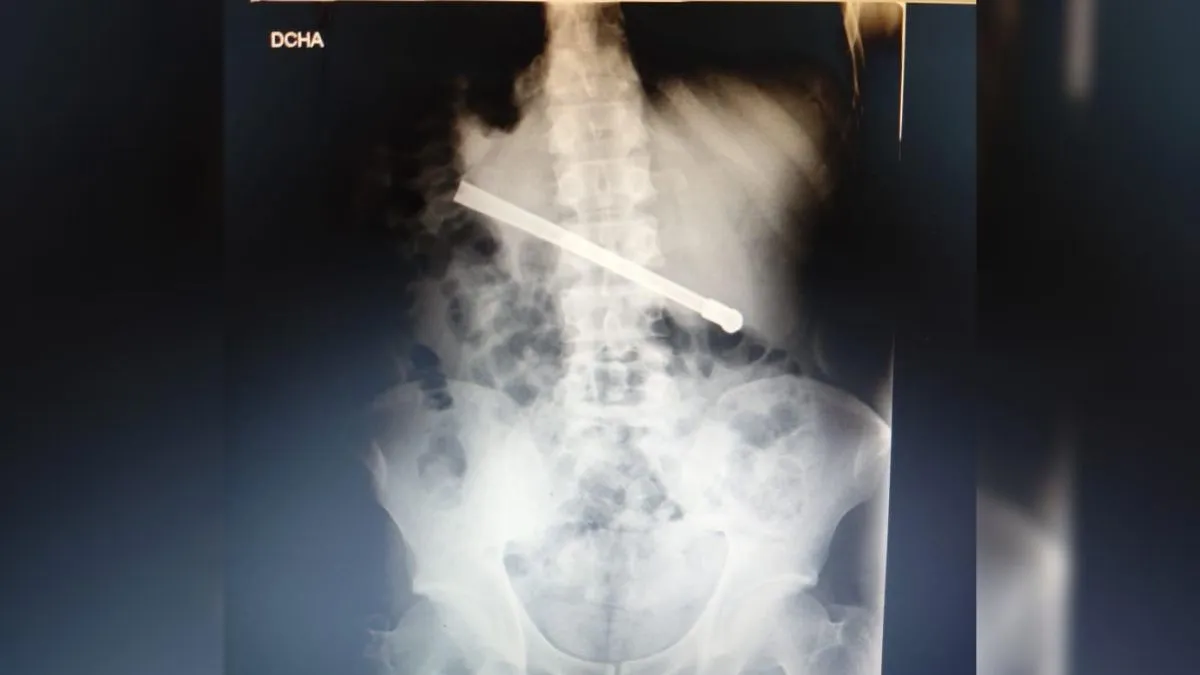

Dolor abdominal: tenía una bombilla

Un preso se quejaba de un dolor abdominal, y se descubrió una bombilla metálica en el estómago.

Allí, una radiografía mostró que tenía una bombilla metálica en el estómago.